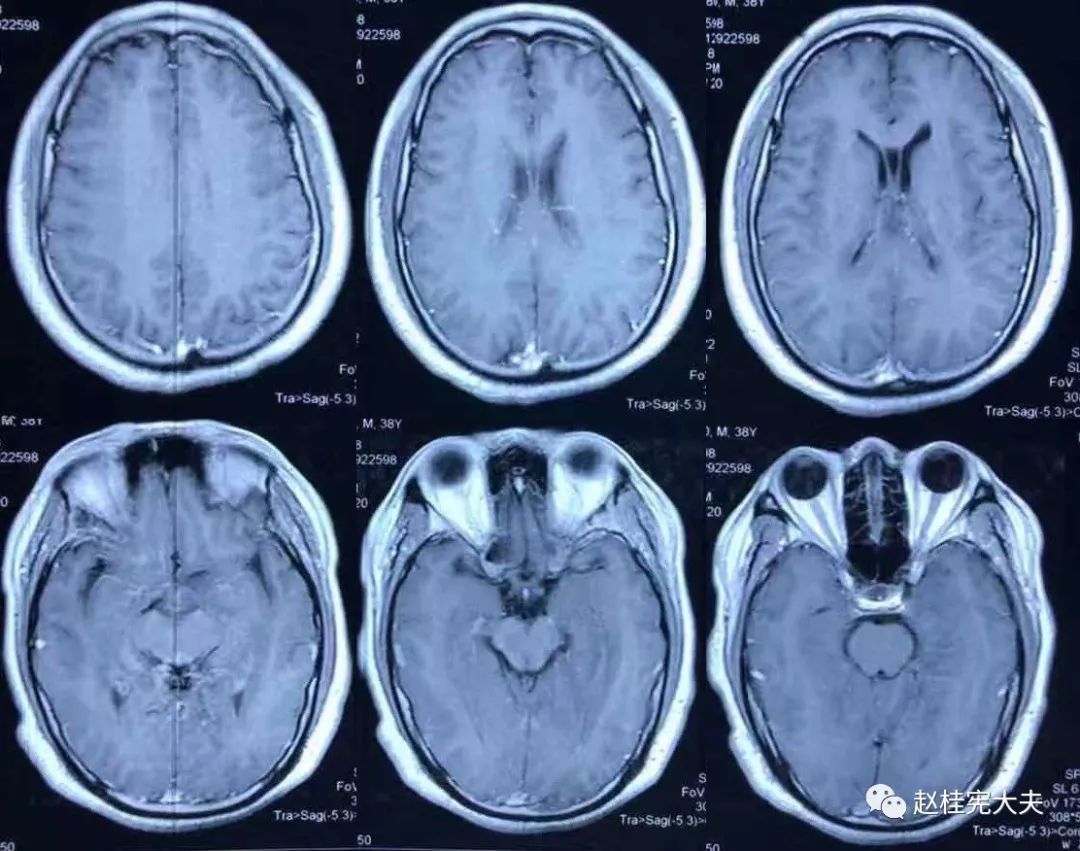

2018.7.6头颅MRI:胼胝体、穹隆及双侧脑室旁、基底节区、右侧延髓、桥臂异常信号,脱髓鞘病变考虑。头颅MRS:左枕叶病变区MRS显示:NAA下降,Cho升高,Cho/NAA=3.86,并见倒置乳酸峰。

2018.7.10磁共振增强:脑室周边病灶轻度强化。

7.20复查头颅MRI平扫:胼胝体、穹隆及双侧脑室旁、基底节区、右侧延髓、桥臂广泛信号异常,对照前片(7.10)范围明显缩小。

2018.10复查头颅MRI:胼胝体压部、左侧部分枕颞叶、侧脑室枕角旁、中脑脱髓鞘病变,视神经脊髓炎谱系病?结合对照前片(7.4)病变范围有所缩小。

我看到患者时的思考:当了解了患者前期诊疗经过后,在看到患者磁共振片子时,我的第一反应就是淋巴瘤。尽管患者激素治疗后症状有好转,病灶在磁共振上看起来也是有好转,但淋巴瘤也会出现这样的表现。

我对满脑室边的病灶的体会是:遇到这样的病例,首先要考虑感染、肿瘤(如室管膜瘤、生殖细胞瘤、淋巴瘤或转移瘤脑室播散等等),炎症要放到后面去考虑,脱髓鞘的诊断要打个大大大大的?。炎症中,血管炎不像,自免脑也不是很支持,尽管边缘系统似乎也有受累,但患者边缘叶脑炎的精神、行为异常、癫痫等症状很少,而且磁共振上看去除了边缘系统,整个脑室系统都有受累,这个和常见自免脑不符。视神经脊髓炎谱系病?尽管病灶在水通道蛋白富集区,但这样的视神经脊髓炎(视神经和脊髓均未受累,近脑室边的异常信号)至少罕见,即使诊断,也应该是排除其它的疾病后才可能考虑。

患者住院期间还请眼科会诊,除双眼玻璃体轻度浑浊,视力、视野、OCT均未见明显异常,未建议行玻切明确诊断。患者入院后嗜睡症状有加中,但一直未诉头痛,仅是头昏,静滴甘露醇症状减轻不明显。复查头颅磁共振平扫+增强:病灶范围较前明显扩大。轻度强化。